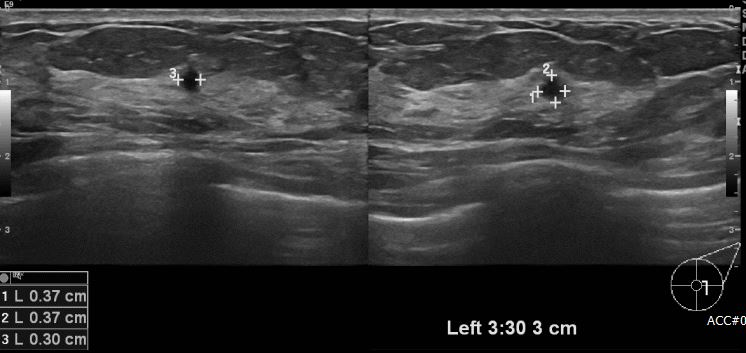

상기 환자  건강검진상 이상 소견으로 내원하신 50대 여성분으로 좌측 3시 30분 방향에서 3cm 떨어진 거리의 혹 조직검사 시행하여 좌측 유관암 진단 되었습니다.